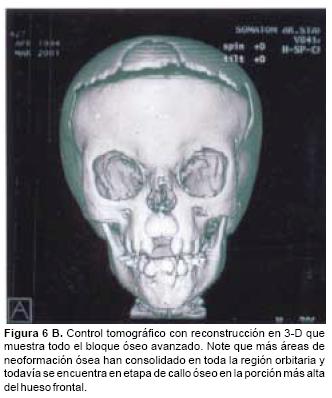

En todos los pacientes se logró el avance planificado de los segmentos óseos, al corregir la deformidad del hueso frontal, el exorbitismo y en la retrusión del tercio medio en los casos con avance en monobloque. Los avances mayores se obtuvieron en el hueso frontal y variaron entre 16 y 30 mm., mientras que los menores fueron los del hueso maxilar que fluctuaron entre 9 y 16 mm. (Cuadro I). Radiológicamente los controles postoperatorios tempranos mostraron inicialmente áreas de hipodensidad ósea, que al final del periodo de consolidación cambiaron a áreas de densidad ósea radiológica normal, lo que significa neoformación de hueso. Las áreas de hueso neoformadas que consolidaron en forma más rápida, son las ubicadas en las líneas de osteotomía de la unión pterigomaxilar, pared lateral de la órbita y unión frontoorbitaria. Las áreas que más tardaron en consolidar incluye la porción lateral y superior del hueso frontal.

También los controles radiológicos durante el proceso de distracción mostraron que no se produjo la creación de espacios muertos intracraneanos durante los avances. En todos los pacientes con sinostosis bicoronal el avance frontoorbitario produjo excelentes resultados estéticos dando una nueva forma a la región frontal y proyectando mejor el reborde supraorbitario. En los niños con enfermedad de Crouzon y síndrome de Apert, se corrigió en forma muy satisfactoria el exorbitismo al resolver las graves exposiciones corneales (Figuras 5 A, B, C, D, E, F, G, H), en los que se utilizó el avance simultáneo del tercio medio, este cambio óseo corrigió muy satisfactoriamente la retrusión del mismo, ampliando la vía aérea y resolviendo en muchos casos grandes problemas ventilatorios durante el sueño (Figuras 6 A, B, C, D, E, F). Los pacientes con plagiocefalia corrigieron significativamente la deformidad frontoorbitaria y los tejidos blandos suprayacentes se adaptaron a la nueva estructura ósea. La clásica órbita de arlequín de estos niños producida por la sinostosis del frontal con el esfenoides, inmediatamente se ve corregida en su forma y su configuración se hace muy similar con la órbita contralateral (Figura 7)(Fig. 7a, 7b, 7c, 7d, 7e, 7f, 7g) (Cuadro II).

En conclusión la distracción ósea asistida endoscópicamente es una excelente alternativa terapéutica para el tratamiento de los grandes síndromes craneofaciales, produciendo resultados estéticos y funcionales altamente satisfactorios en estos pacientes. Disminuye en forma muy importante el porcentaje de complicaciones, y por las áreas de neoformación ósea en las líneas de osteotomía asegura la estabilidad de los resultados en el largo plazo. Por el hecho de tratar niños, será fundamental observar el crecimiento y desarrollo del esqueleto craneofacial en los siguientes años a fin de establecer los criterios adecuados de sobrecorrección hasta su edad adulta.